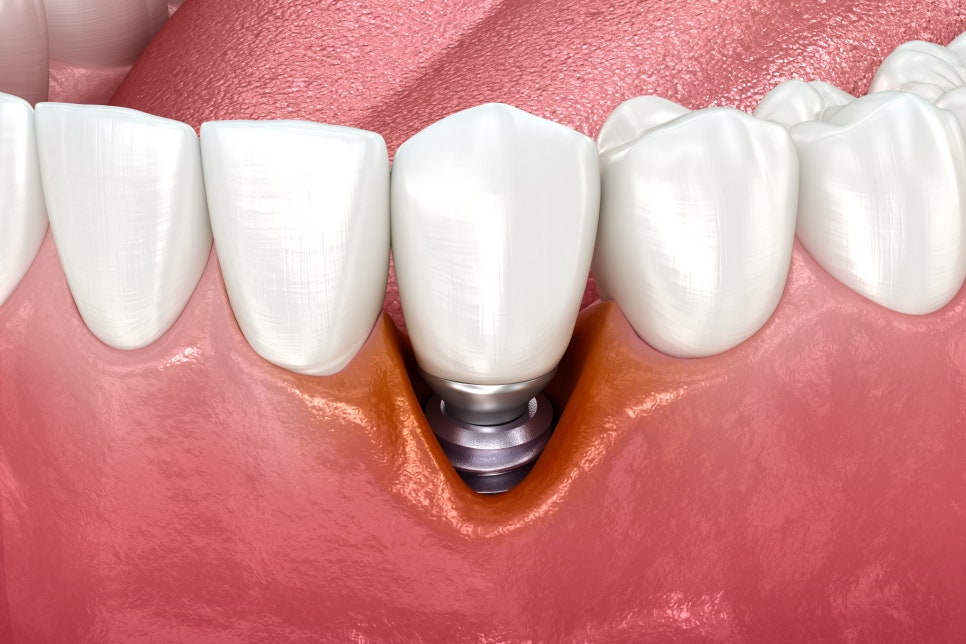

임플란트는 자연치아를 상실하였을 때

대체할 수 있는

가장 좋은 치료 방법 중 하나로

사후관리만 잘 이루어진다면

반영구적으로 사용할 수 있기 때문에

장기적으로 봤을 때는

경제적인 치료이지만

구강 위생 관리를 소홀히 하게 된다면

임플란트 주위염이 발생하여

주변 잇몸뼈가 흡수되고 소실되어

심한 경우에는

식립해둔 임플란트가 탈락하는 일이

생길 수도 있습니다.